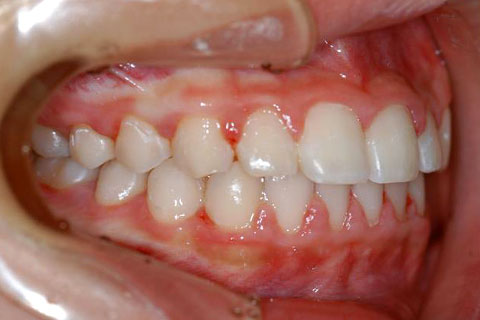

受け口(反対咬合)の症状

下あごが上あごより突出しているか、上あごが下あごより後退している状態で、咬み合わせが逆になっているので反対咬合ともいいます。お子様の場合、受け口(反対咬合)を放置していると、成長期において下あごが過大に成長し悪化しますので、出来る限り早い時期に治療することをおすすめします。受け口(反対咬合)は見た目の問題だけでなく顎の動きを制限し、将来的に顎の痛み(顎関節症)を引き起こす場合があります。また、お子様の場合は、正常な上顎の成長を阻害する可能性があります。

受け口(反対咬合)の症例